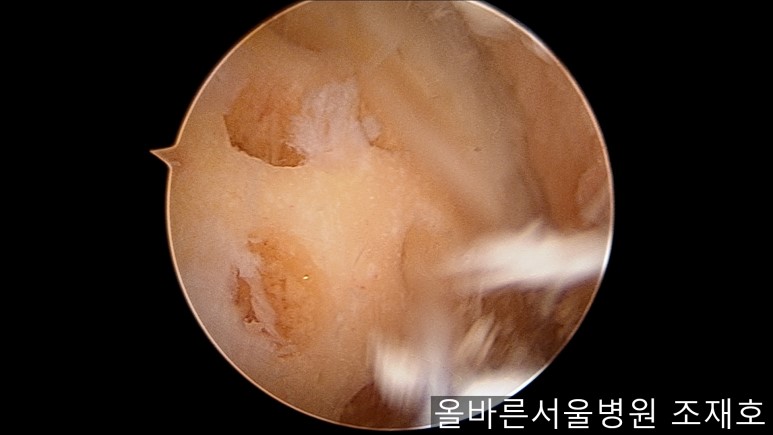

与内侧对照,外侧的软骨及软骨板无损伤。

为了软骨再生,在胫骨上端进行微骨折术。

胫骨上端是通过微骨折术,可再生软骨的地方。

尽量将孔打地细密,确认此处骨髓腔内的血流出。